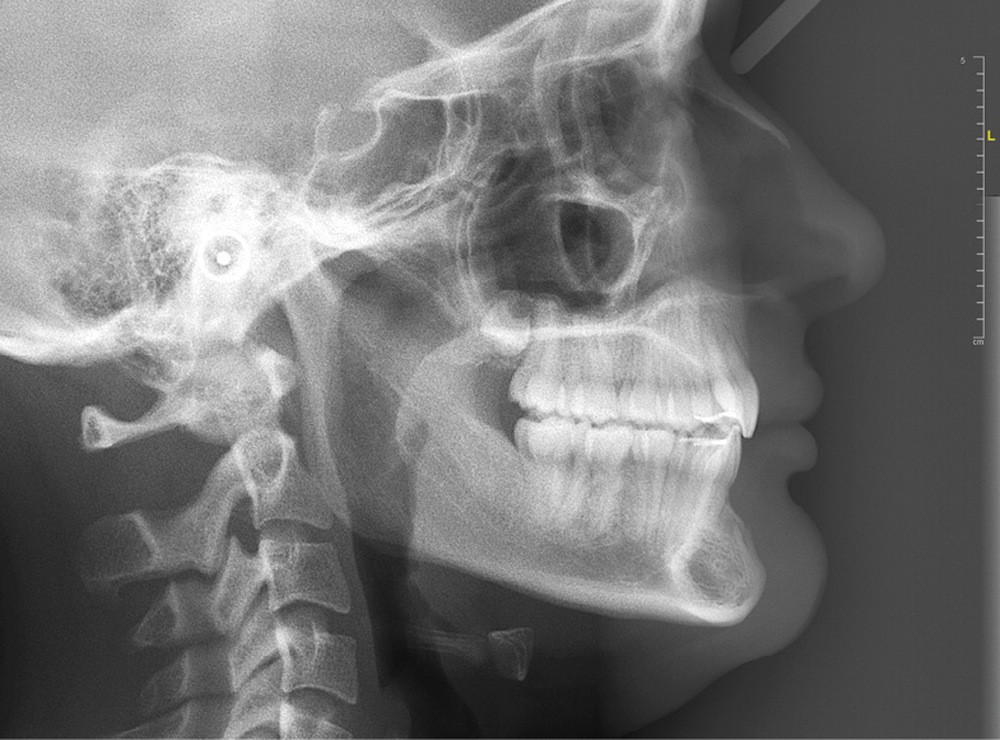

Les examens cliniques et radiologiques ont mis en évidence l’inclusion de 13 et 23, une légère classe II bilatérale par perte d’ancrage, un biotype parodontal de type IV de Maynard et Wilson avec une insertion du frein mandibulaire antérieur papillaire, une biproalvéolie et une typologie hypodivergente. La réalisation d’un examen tridimensionnel a permis de confirmer la localisation palatine de 23 et vestibulaire de 13 ainsi que de visualiser l’étendue des résorptions radiculaires touchant 12, 21 et 22 (fig. 1a-i).

Les résorptions radiculaires des dents adjacentes aux canines maxillaires incluses sont en effet fréquentes avec un risque plus important chez les femmes. La localisation sagittale de la canine incluse constitue un facteur de risque dans la présence de résorptions radiculaires [3]. Le recours aux examens tridimensionnels est donc indispensable dans le traitement de ces cas.